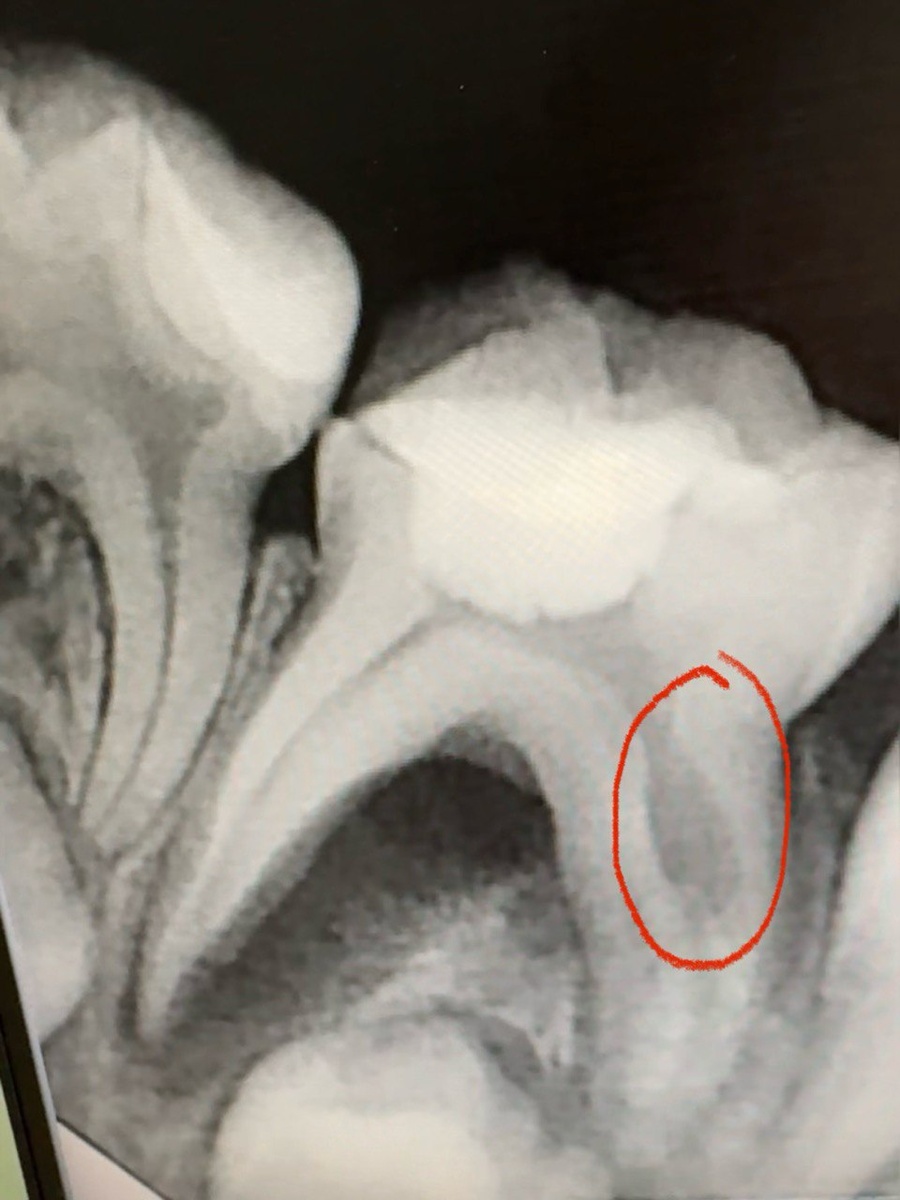

1. Обратите внимание, листая вбок снимки, вы можете увидеть на втором фото выделенную красным цветом зону очага воспаления. Достаточно обширная, уходит в межкорневое пространство.

И 1 и 2 - это показание к удалению зуба. И конечно, эти изменения не могли произойти за 2 недели, на это нужно гораздо больше времени.